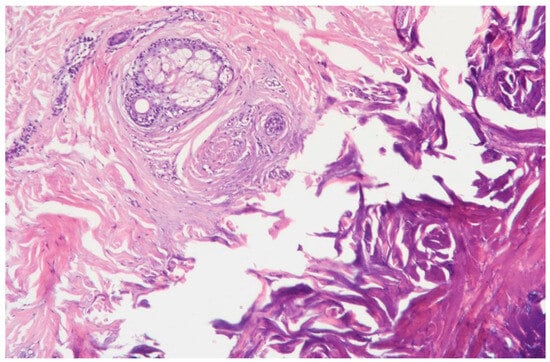

3.1.1. Clinical Case 1: Soft Tissues in the Dissection Area, Scar 10 W (See Figure 2)

Description: The histological examination revealed total necrosis of the epidermis and dermis, with the formation of a demarcation zone heavily infiltrated by polymorphonuclear leukocytes. The infiltrate extended into the subcutaneous adipose tissue. The vessels within the necrotic zone were coagulated, while those in the underlying tissues were markedly dilated. Small diapedesis hemorrhages were noted. The skin appendages in the underlying tissues remained intact, and the collagen fibers were preserved.

Figure 2.

Skin changes in Rat 1 on the 7th day after exposure to the thulium laser at 10 W, 65 Hz. H&E staining, 10× objective magnification.